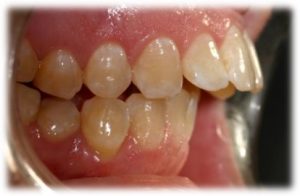

אחת התופעות עליהן מתלוננים רוב המתרפאים ממוצא אירופאי היא בליטה של השיניים הקדמיות העליונות.

במקרים בהם ישנה צפיפות גדולה מאוד של שיניים ו /או בליטה גדולה שלהן כלל הטיה אלכסונית שגורמת לליקוי אסתטי יפנה האורתודונט את המתרפא/ה לעקירות שיניים קבועות.